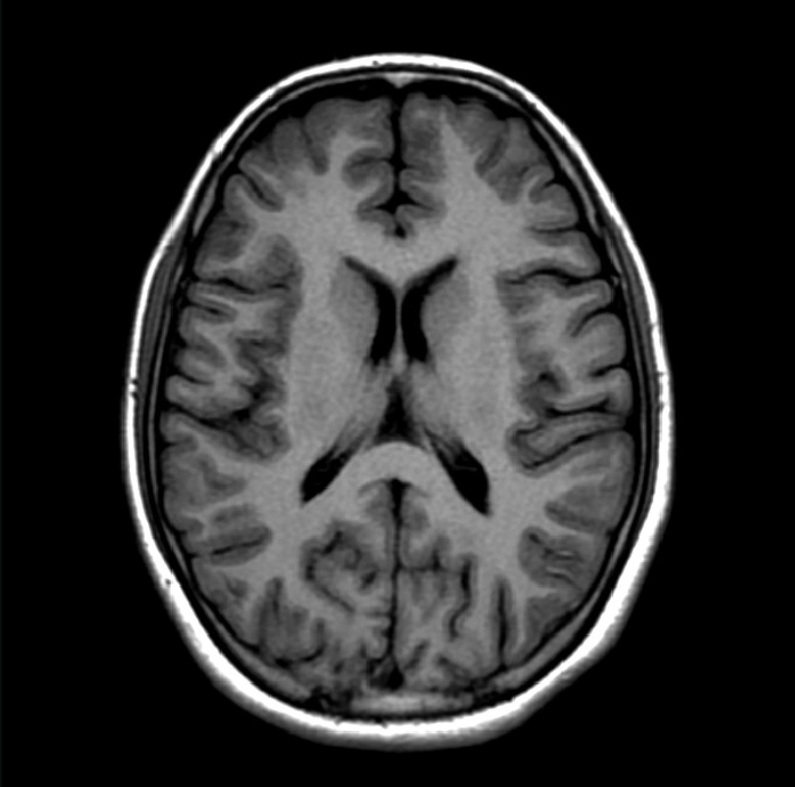

The MRI machine takes images from different angles, and our lab uses three main views of the brain.

• The axial view takes vertical slices from the front to the back of the head. This is a head-on look at the brain.

Axial View